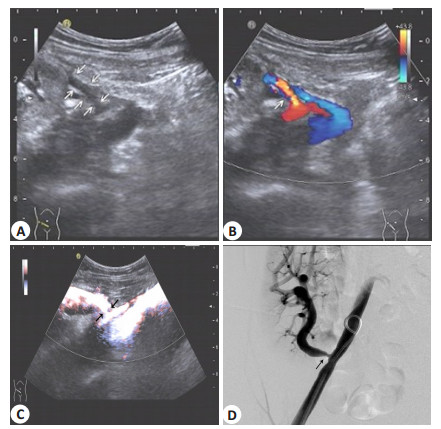

患者出现不明原因的肌酐进行性或反复升高(>20%),伴或不伴顽固性高血压、尿量减少即进行超声检查,超声图像提示移植肾动脉可疑狭窄则可初步诊断TRAS,收缩期峰值血流速度>200 cm/s则进一步支持TRAS诊断,再进行数字减影造影(DSA),确诊为TRAS(图 2)。

|

图 2 TRAS超声检查图像(箭头示狭窄部位) Figure 2 Ultrasound scan and digital subtraction angiography (DSA) for transplant renal artery stenosis (TRAS) (arrows show site of stenosis). A: Two-dimensional ultrasound image of TRAS; B: Color Doppler ultrasound image of TRAS; C: Power Doppler ultrasound image of TRAS; D: DSA of TRAS. |